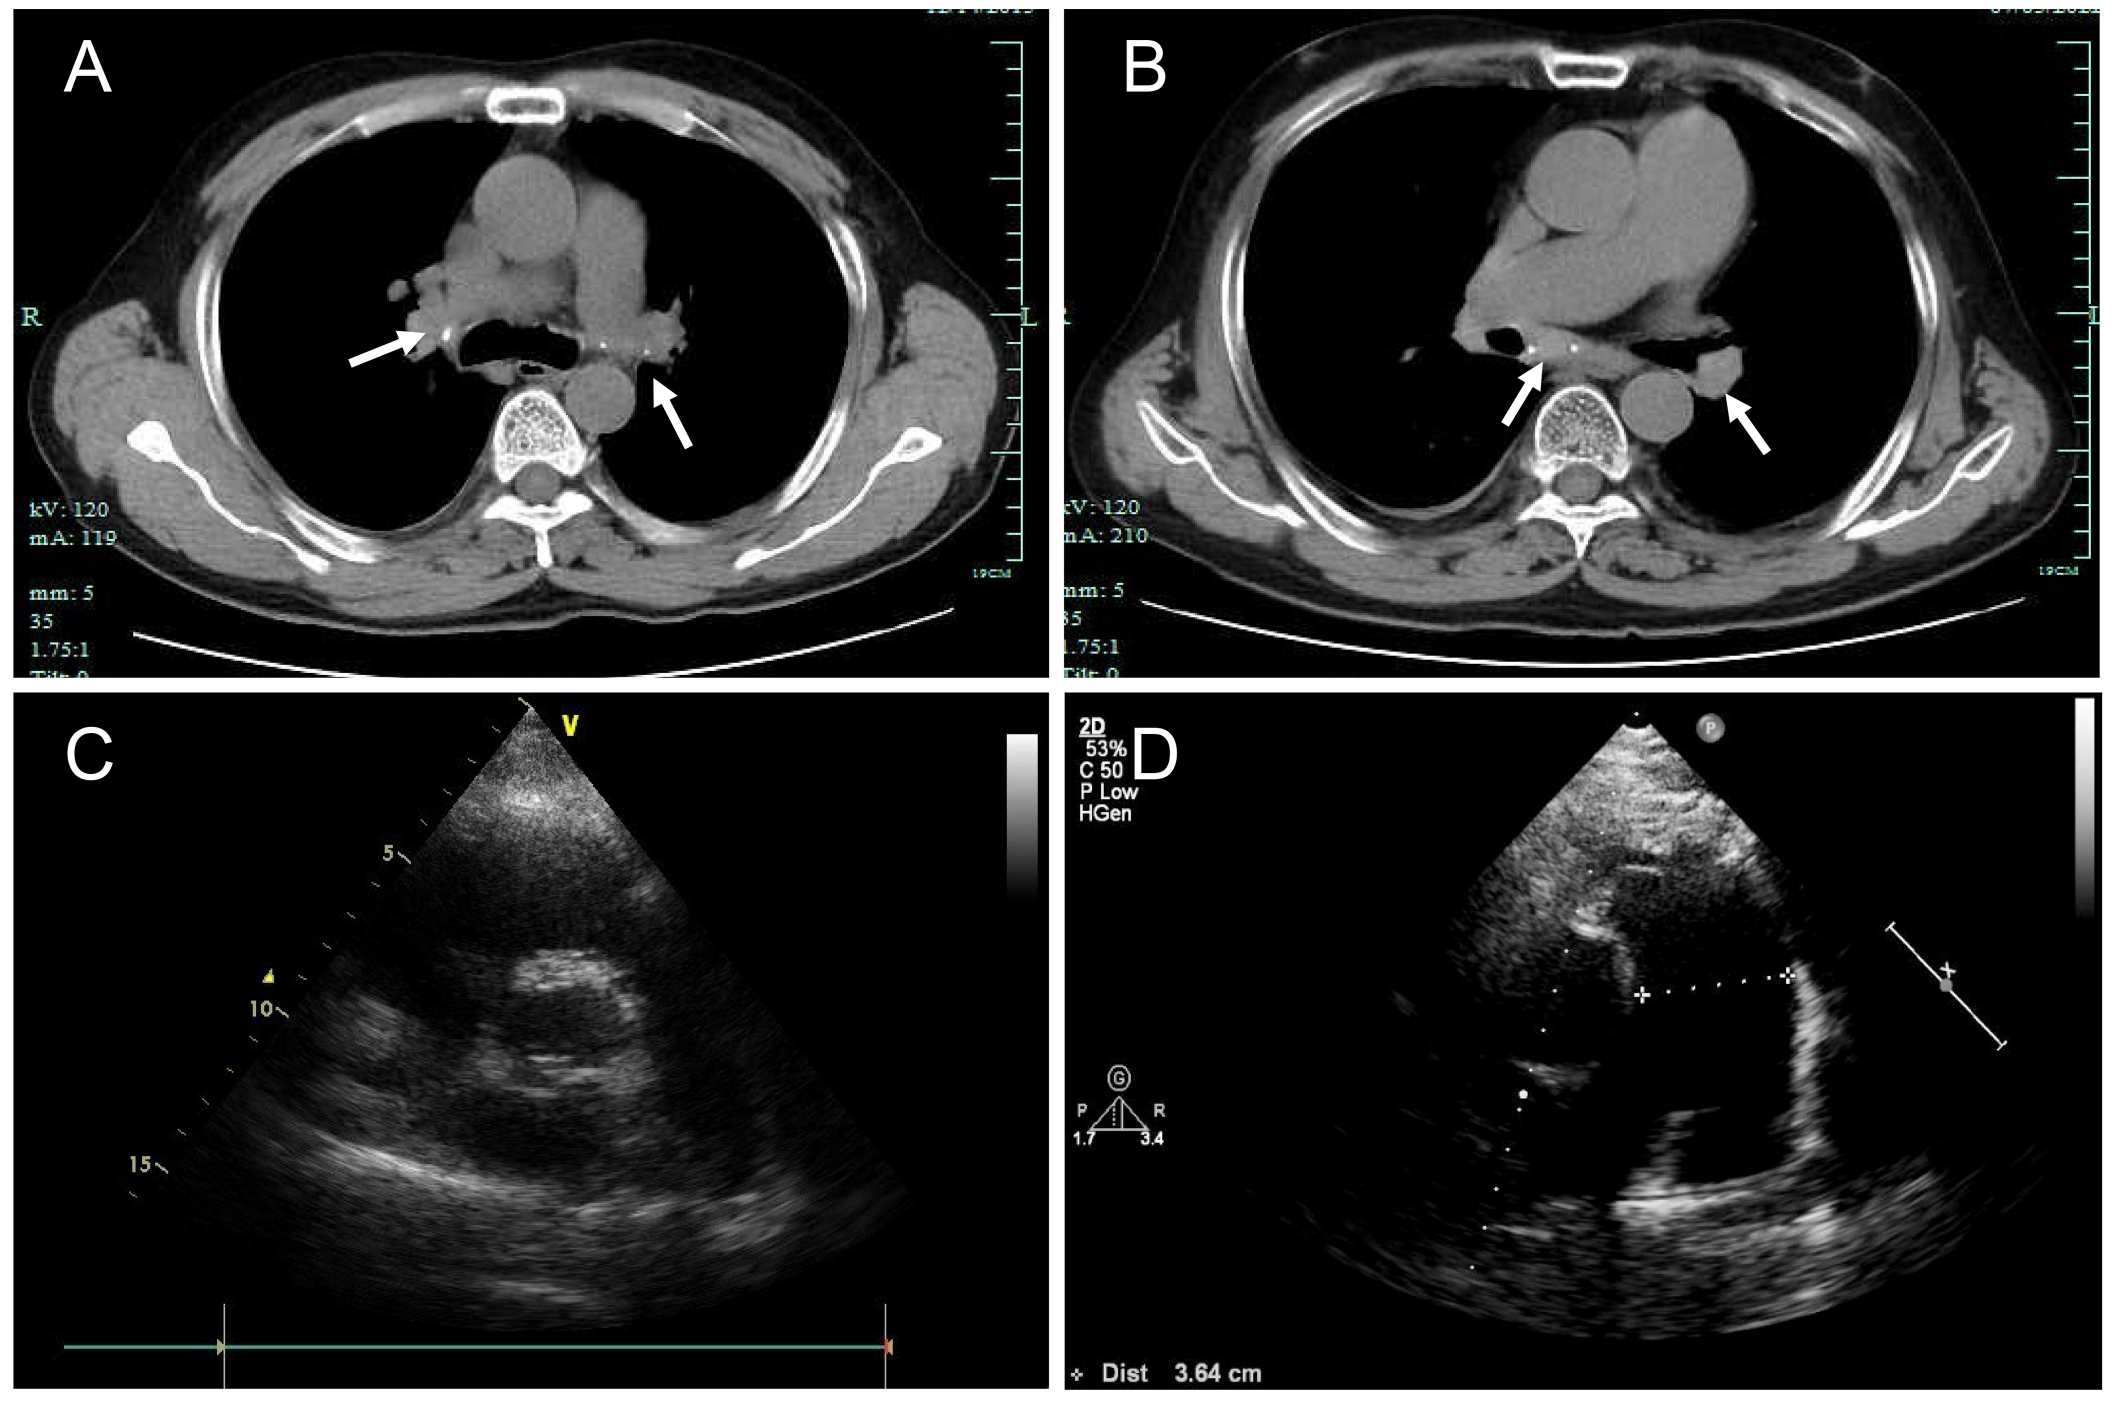

Abstract Body (Do not enter title and authors here): Introduction:Fibrosing mediastinitis is a rare condition characterized by excessive fibrous tissue proliferation in the mediastinum, leading to compression of vital structures. We present a case of idiopathic fibrosing mediastinitis with progressive pulmonary hypertension and multi-vessel stenosis, highlighting diagnostic challenges and management strategies. Research Questions: The case explores the clinical and imaging features of fibrosing mediastinitis, its differentiation from other causes of pulmonary hypertension, and the potential treatment options for fibrosing mediastinitis-related vascular obstruction. Aims: This case aims to (1) describe the clinical course and diagnostic pitfalls in a patient with long-standing fibrosing mediastinitis, (2) evaluate the role of imaging and invasive testing in diagnosis, and (3) assess the efficacy of endovascular stenting in symptomatic relief. Methods: A 58-year-old male with a 5-year history of recurrent dyspnea and chest tightness underwent serial evaluations, including CT angiography, echocardiography, pulmonary function tests, bronchoscopy, and right heart catheterization. After failing medical therapy, he underwent percutaneous pulmonary artery stenting. Results: Imaging revealed mediastinal lymphadenopathy with calcification, pulmonary artery stenosis, and tracheobronchial compression. Pulmonary arteriography confirmed severe stenosis in multiple pulmonary arteries. Stent implantation improved exercise capacity (6-minute walk distance: 360m to 485m) and oxygen saturation. Conclusions: Fibrosing mediastinitis is a rare but treatable cause of pulmonary hypertension. A high index of suspicion is needed in patients with progressive dyspnea and mediastinal fibrosis. Endovascular stenting may provide symptomatic relief in select cases, though long-term outcomes require further study.